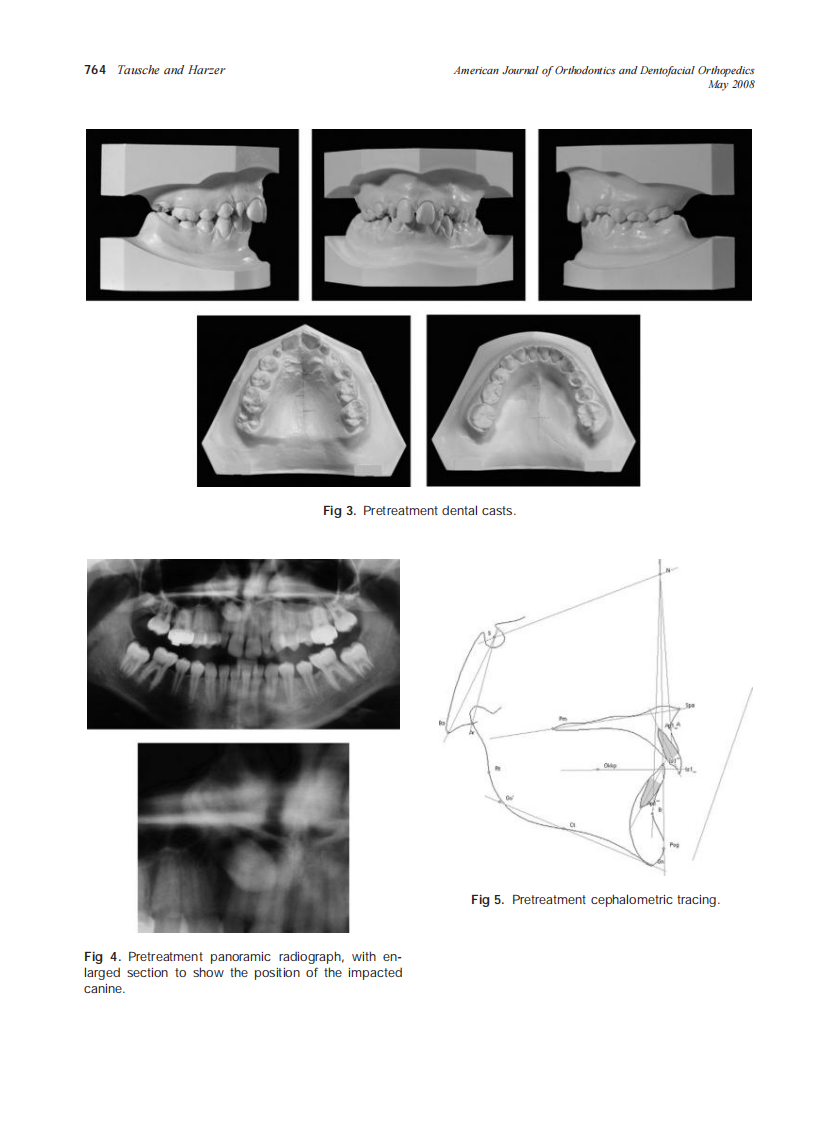

2008_133_5_762_770_Tausche.pdf